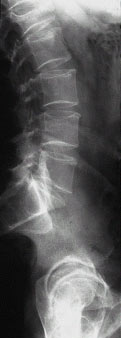

Abb.4+5 von links

Bruch des 1. Lendenwirbelkörpers nach einem Sturz eines 60 jährigen Patienten